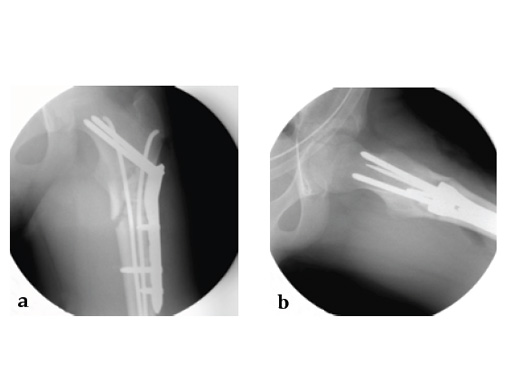

Case 1: LCP PHP 130. A 15-year-old boy sustained a refracture of a pathological fracture of the subtrochanteric region following a severe trauma, previously fixed with ESIN , diagnosis: juvenile bone cyst.

Case provided by Theddy Slongo, Bern, Switzerland